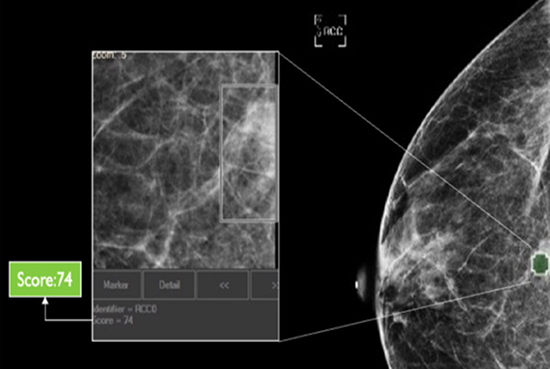

Which Patient to Spend More Time on?

The software also generates a unique, data-driven neuScore™ that provides radiologists with a quantitative measure of suspiciousness in a marked region of interest, ranging from 0 (least suspicious) to 100 (highly suspicious). This score can be tracked over time to evaluate the stability or evolution of identified anomalies.